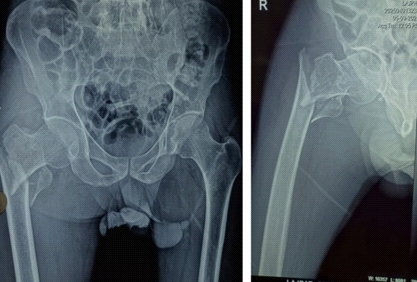

一例50岁男性患者的病例,该患者患有晚期PVD,并在家摔倒后发生右股骨转子间骨折。

尽管术中过程顺利,但在术后期间,患者出现了急慢性肢体缺血,表现为远端灌注和组织活力逐渐丧失。尽管迅速进行了抗凝治疗、筋膜切开术等等,仍无法挽救肢体。